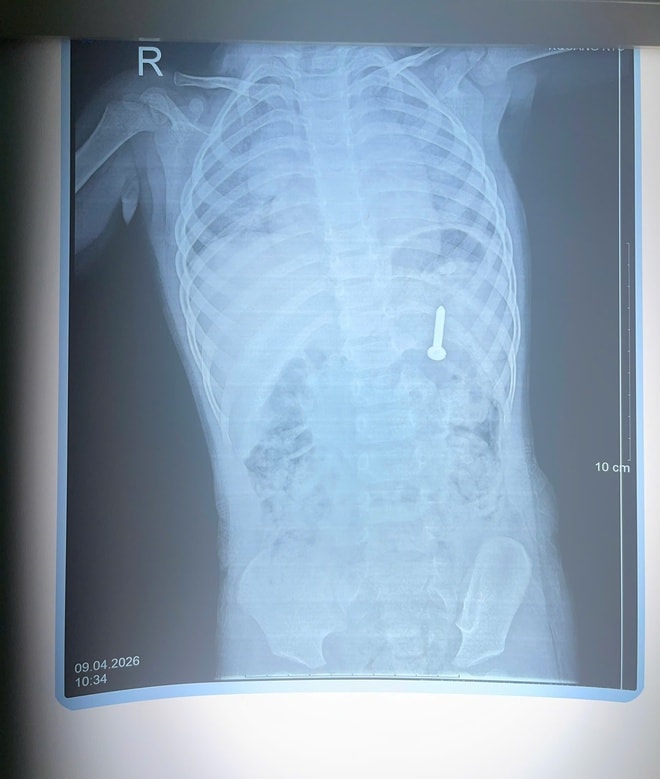

Bé 21 tháng tuổi nuốt phải đinh vít dài khoảng 2,5cm- Ảnh 1.

Dị vật đinh vít.

Qua thăm khám và chụp X-quang, các bác sĩ xác định dị vật nằm trong dạ dày. Nếu không được xử lý kịp thời, dị vật có thể gây thủng đường tiêu hóa, xuất huyết và nhiều biến chứng nguy hiểm.